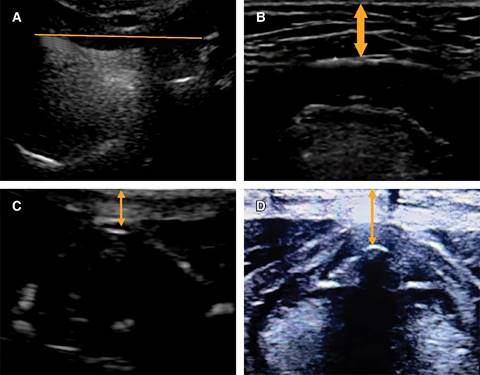

Distancia hiomental: el paciente en posición supino con cabeza y cuello en posición neutra sin almohada utilizando ecógrafo con el transductor se mide la distancia desde el borde anterior del hueso hioides hasta el borde posterior del mentón.

Distancia piel-hueso hioides: el paciente en posición supino con cabeza y cuello en posición neutra sin almohada utilizando ecógrafo con el transductor lineal, en eje corto y con una inclinación entre 30-45 grados en dirección cefálica, se realiza la medición.

Distancia piel-epiglotis: el paciente en posición supino con cabeza y cuello en posición neutra sin almohada utilizando ecógrafo con el transductor lineal, en eje corto y con una inclinación entre 30-45 grados en dirección cefálica, se realiza la ubicación de la línea media entre el hueso hioides y el cartílago tiroideo a nivel de la membrana tirohioidea con grados variables de angulación cefálica y caudal. La epiglotis se observa como una estructura discretamente móvil, por lo que se realiza la medición

Distancia piel-cuerdas vocales: se realiza en las mismas condiciones con un eje corto, a nivel de las cuerdas vocales se procede a realizar la medición de la distancia entre la comisura anterior de las cuerdas vocales y la piel (Figura 1).

Figura 1: A) Distancia hiomental. B) Distancia piel a hueso hioides. C) Distancia piel a epiglotis. D) Distancia piel a cuerdas vocales.